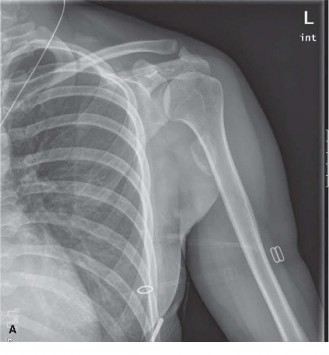

A 28-year-old, recreational athlete presents to your clinic with shoulder pain and a history of multiple subl…